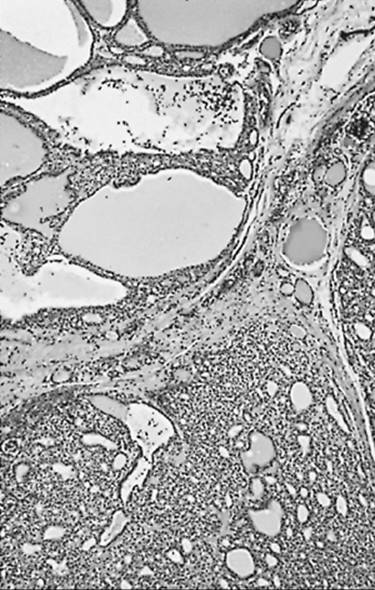

Microscopically, a typical adenomatous nodule has a varied pattern consisting of large and small follicles, usually with a large amount of colloid present (Figs. 21.5 and 21.6.). Giant follicles (colloid cysts), often irregular in shape, are common. The cells range from flat to cuboidal or columnar, and their nuclei are small, rounded, uniform, and compact. The stroma often appears loose and edema tous. Chronic inflammation, groups of macrophages, hemosiderin, fibrosis, and even calcification can be found.

FIGURE 21.5. Adenomatous nodules. The lower left nodule is solid; the upper right nodule has undergone cystic degeneration.

FIGURE 21.6. Adenomatous nodules. The nodule at the upper left contains large colloid-filled follicles.